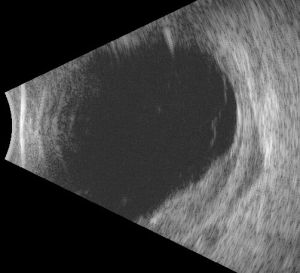

The dominant early sign is multifocal, yellow choroidal swellings on fundus exam. They can resemble multifocal choroiditis or birdshot choroidopathy.[16] Aronow et al. found that of 34 effected eyes, all of them showed yellow-white choroidal infiltrates on ophthalmic examination.[1] Uveal tract thickening can also be seen on fundoscopy, which contributes to the serous retinal detachment often seen.[16] Choroidal folds are common due to the thickened choroid. One hallmark of a choroidal lymphoma is the presence of extra-scleral extension of the choroidal mass, which is often seen with ultrasound imaging. Images 1 and 2 demonstrate choroidal thickening, choroidal folds, and hyper-autofluorescent flecks in the macula in a patient presenting with uveal lymphoma.

Ancillary imaging can help to understand the extent of the disease. B-scan ultrasonography can reveal extrascleral extension (ESE) with the most common pattern being crescentic thickening outside of the posterior scleral margin. These ESE are often concentrated in the posterior aspect of the globe near the optic nerve, though they can be seen more anteriorly. Aronow et al. found that in 75.9% of cases, B-scan ultrasonography revealed ESE. In their case series, indocyanine green angiography (ICG) also revealed focal regions of hypofluorescence which corresponded to the choroidal infiltrates seen on clinical examination.[1]